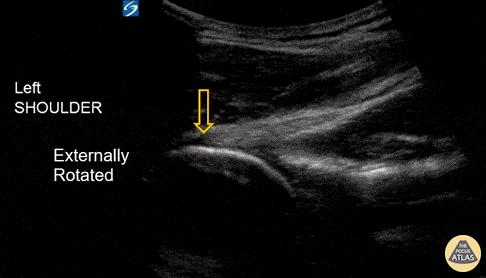

An 18-year-old male with acute left shoulder pain after a physical altercation in which his left arm was pulled. Video clip reveals the left humeral head sliding in and out of the glenoid fossa with internal and external rotation, confirming the diagnosis of shoulder subluxation. Read more about the case and shoulder POCUS on: https://www.aliem.com/ultrasound-for-win-acute-shoulder-injury-us4tw/ Mark Rivera-Morales, MD, PGY-3 Fernando Rivera, MD, PGY-3 Javier Rosario, MD, FACEP @javimedsimus UCF/HCA Emergency Medicine Residency Program of Greater Orlando. Osceola Regional Medical Center @UCFEMOrlando